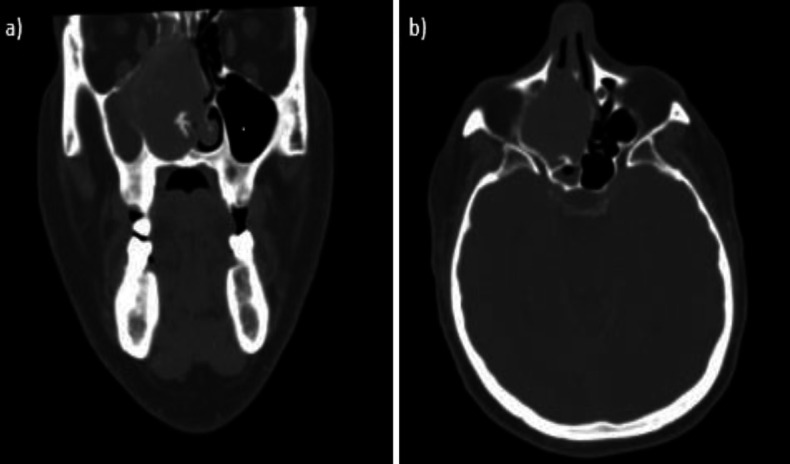

Case report: This case report shows a rare right nasal septal solitary fibrous tumor, which was surgically removed using a trans-nasal endoscopic technique. For the first time, the mass was decomposed by a plasma blade, and the implant site was treated by performing a subperiosteal removal of septal mucosa and cartilage. Histopathological examination confirmed the diagnosis of solitary fibrous tumor. Follow-up at three, six, and twelve months showed no signs of relapse.